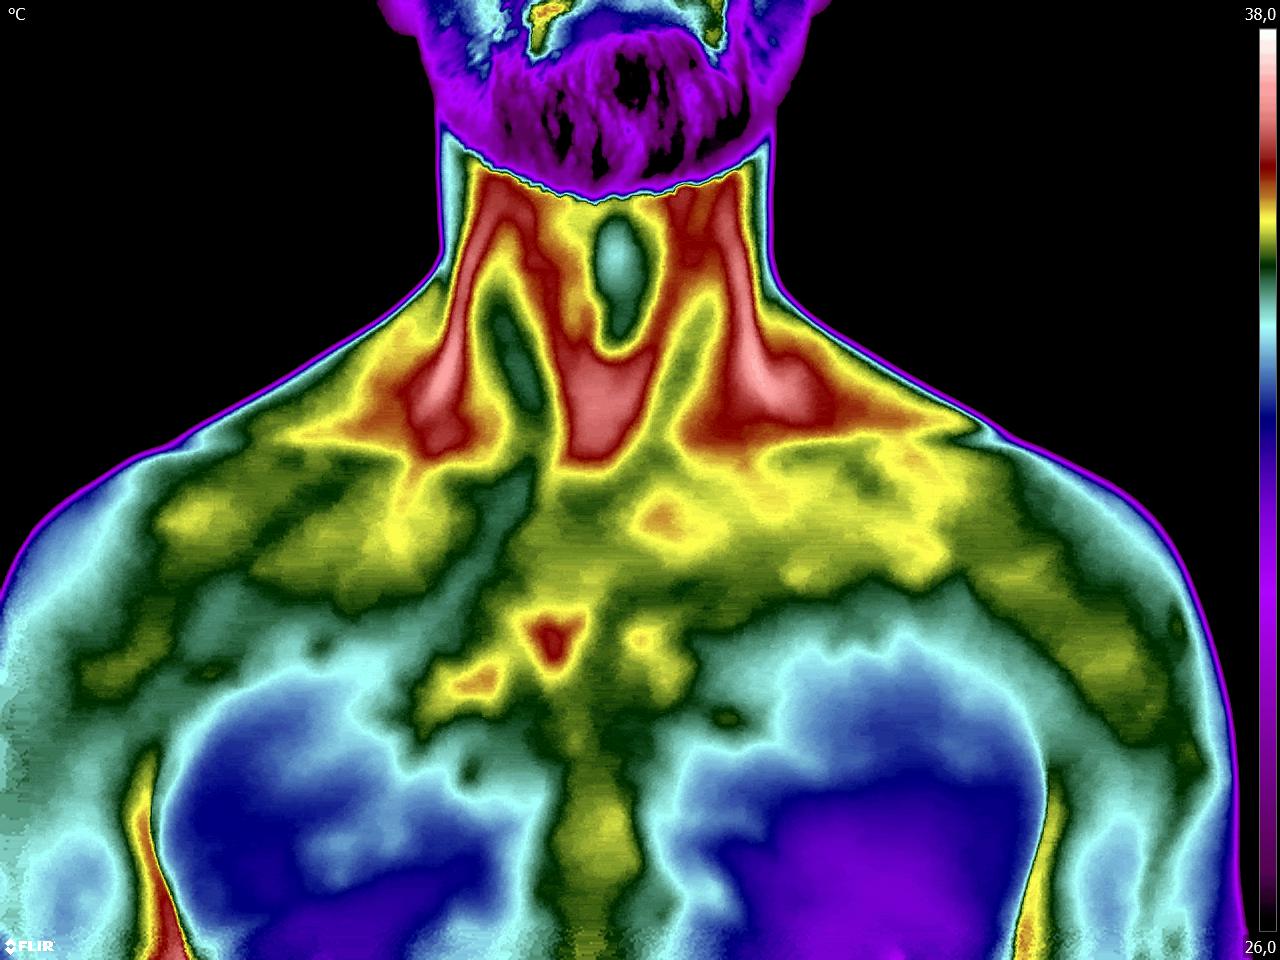

Colega fisioterapeuta e terapeuta ocupacional, vocês sabiam que com o estudo da Técnica Termofuncional vocês podem detectar alterações que fundamentam […]

Colegas fisioterapeutas e terapeutas ocupacionais, vocês sabiam que com o estudo da Termofuncional é possível determinar a disfunção do se […]